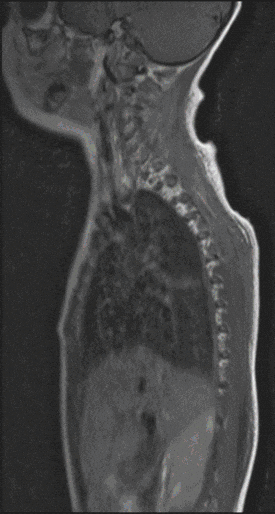

Spinal Cord Tumors

In most cases, the tumors of the spinal cord are histologically similar to the tumors of the brain. However, the treatment strategy differs significantly from operations on the brain. Tumors can arise outside the spinal cord and compress it massively, or they arise inside the spinal cord and can drive it up from the inside. Both pose a threat to function with the consequence of spinal cord syndromes (e.g. paraplegia).